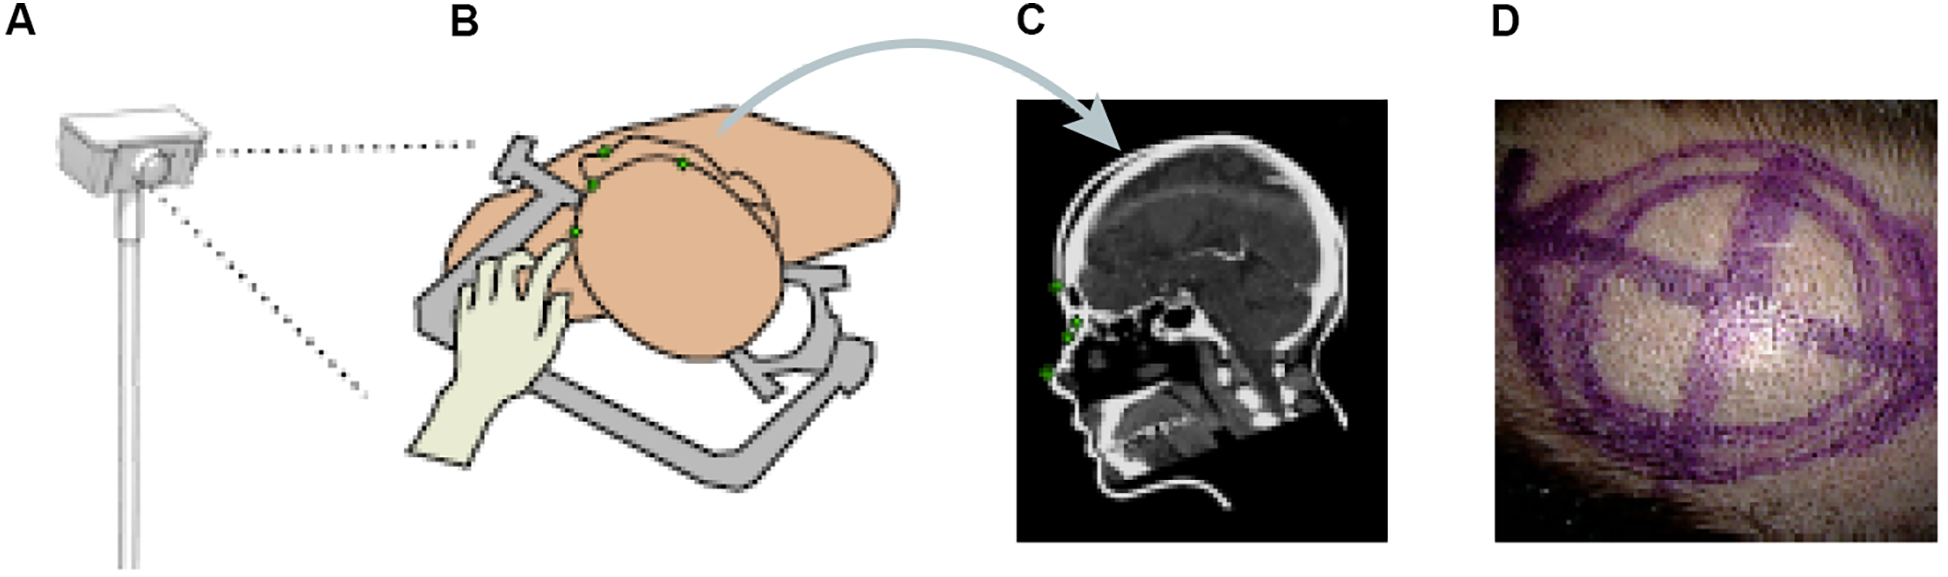

Other papers have also proposed ML methods to track objects or hands' movements in surgery. Kögl et al. published a study in 2022 describing the use of ML to track the movements of hands via hand topology (8). This tool-free neuronavigational method focused on 21 landmarks assigned to a hand and used real and synthetic images to train 2 deep learning networks to estimate hand pose. Real images were used to understand the 2-dimensional coordinates of the hand, whereas synthetic images were used to train the model on relative depth. The Google MediaPipe ML framework was implemented to determine the 2.5-dimensional hand pose. However, the aim was to estimate the 3D pose. Therefore, once these images had been used to train the neural networks, solving the Perspective-n-Point problem was then necessary. This was done by determining where the hand was in space relative to the frame, allowing the determination of the 3D hand pose. Once the 3D hand pose had been estimated, these coordinates were inputted into the 3D Slicer using the OpenIGTLink. The overall aim was to have tool-free neuronavigation that would allow the estimation of hand pose to allow neurosurgeons to use their fingertips to plan craniotomies instead of conventional pointers (Figure 12) (8).

Machine learning (ML) application in neurosurgery tool-free methods. In an ML-based hand pose estimation study, Kögl et al. (8) presented a new tool-free neuronavigation method using an RGB camera during burr hole placement. This figure shows the stepwise process used to track hand motion for landmark selection. (A) Illustration of the monocular RGB camera used for this experiment to capture the motion of the hand. (B) Illustration of the hand being used to select landmarks for burr hole placement. (C) Computed tomography showing predefined anatomical landmarks. (D) Photograph showing the final position of the burr hole placement for a craniotomy using this system. Used with permission from Kögl FV, Léger É, Haouchine N, et al. A Tool-free Neuronavigation Method based on Single-view Hand Tracking. Comput Methods Biomech Biomed Eng Imaging Vis. 2023;11(4):1307–1315. doi:10.1080/21681163.2022.2163428.